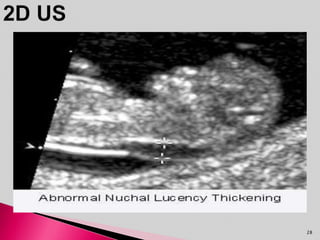

• Nuchal Translucency(NT) refers to the normal

subcutaneous fluid filled space between the back of

the neck and underlying skin.

NT measurement Chance of normal birth

≤ 3.4mm 95%

3.5 – 4.4mm 70-86%

4.5 – 5.4mm 50-77%

5.5 – 6.4mm 67%

≥ 6.5mm 31%